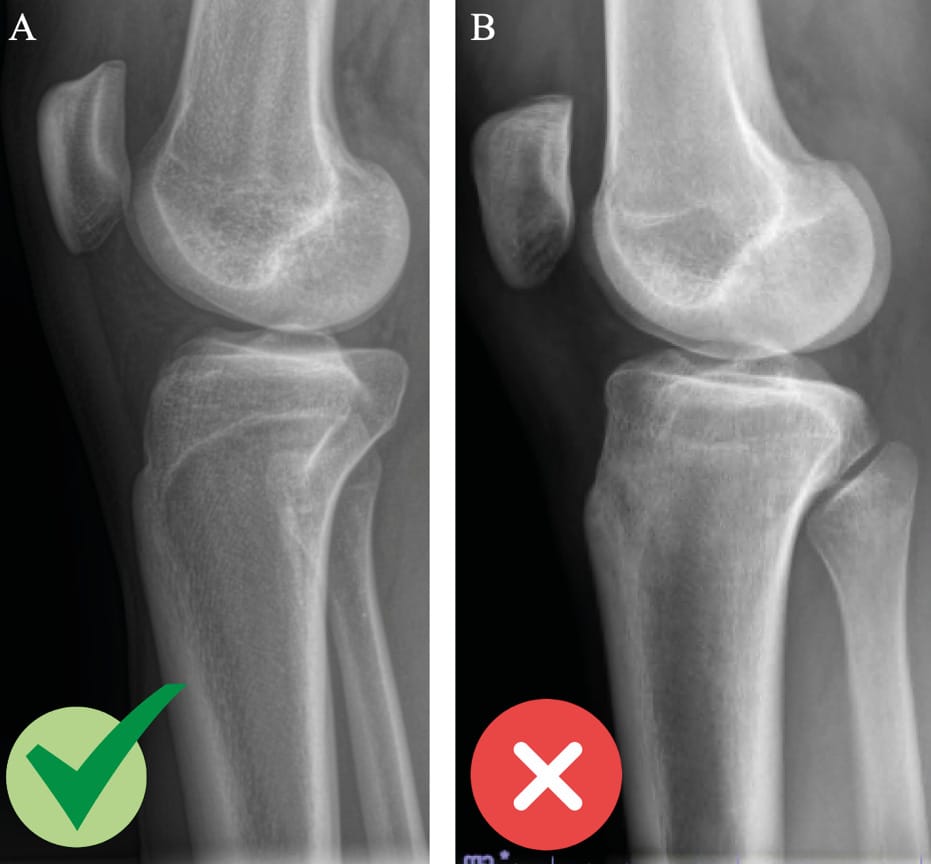

Radiology images should be obtained to include true lateral views showing 15 cm of proximal tibia with 20° of flexion in single-leg weight-bearing. The condyles will be aligned under fluoroscopy before the conventional radiography is performed. Any deviation from lateral will lead to distortions and the measurements will not be possible to interpret [14] Vieider RP, Mehl J, Rab P, Brunner M, Schulz P, Rupp MC, et al. Malrotated lateral knee radiographs do not allow for a proper assessment of medial or lateral posterior tibial slope. Knee Surg Sports Traumatol Arthrosc. 2024;32(6):1462–9. (Figure 1). Next, the technique for measuring the tibial slope must be chosen so that it is reproducible and can be compared from one study to another. It is crucial to choose one method and stick to it. The technique that uses the proximal anatomical tibial axis has a normal value of 9° of slope and the method is described in Figure 2 [15] Brazier J, Migaud H, Gougeon F, Cotten A, Fontaine C, Duquennoy A. Evaluation of methods for radiographic measurement of the tibial slope. A study of 83 healthy knees. Revue de chirurgie orthopédique et réparatrice de l’appareil moteur. 1996;82(3):195–200. . The normal value for SATT is 1.31 mm [16] Cance N, Dan MJ, Pineda T, Demey G, Dejour DH. Radiographic Investigation of Differences in Static Anterior Tibial Translation With Axial Load Between Isolated ACL Injury and Controls. Am J Sports Med. 2024 Feb 1;52(2):338–43. . If translation is posterior, the measurement will have a negative value. The measurement method is described in Figure 3.